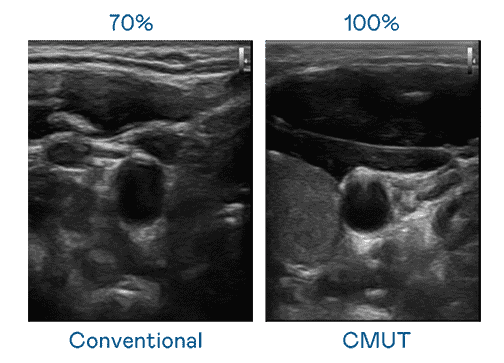

CMUT 技术是一种用电容式微机电元件来产生超音波讯号的技术。。。与传统 PZT 压电式技术相比,,CMUT 频宽增加 30%,,更宽频的超音波讯号让影像解析度大幅提升,,是实现高影像品质医疗超音波扫描、、、、促进精准医疗发展的关键技术。。

大频宽带来超清晰影像

超音波影像的解析度高低,,首先取决于探头能发出的讯号频宽。。。。人生就是博 CMUT 可提供高清晰的超音波讯号,,,,提供高频宽、、高灵敏度、、影像纹理细节更高的超音波影像,,协助医护人员缩短影像判读时间及利用精准的医疗影像进行诊断。。